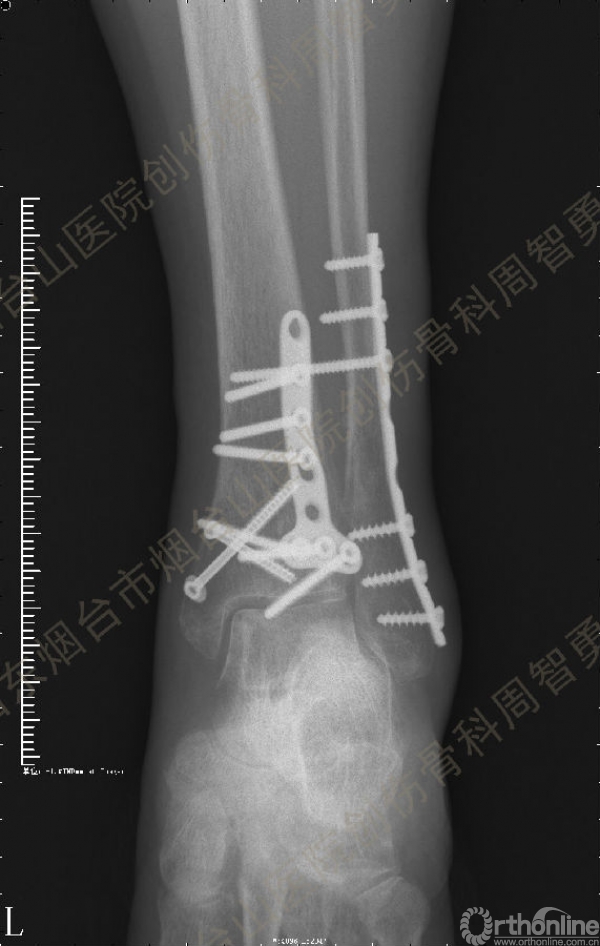

患者一般情况可,左踝关节肿胀,见皮下瘀斑,内、外、后侧有压痛,左踝关节主动运动受限,左足皮肤感觉、血供未见明显异常,左足趾各关节可主动运动。左踝关节正位X线片和CT重建示内踝内上方双层骨皮质影(图1a,c),CT示后侧骨折块分为后内侧骨折块和后外侧骨折块(图2a,b),后内侧骨折块累及内踝后丘,后丘骨折线呈冠状位(图2c),后内侧骨折块腹侧有向近端塌陷的小块骨软骨骨折块(图2d),CT也显示Chaput骨折块(图1c,2e)。

患者取俯卧位,轻度屈膝,小腿下垫枕使足离开床面。取长约10cm的踝关节后外侧切口,皮肤切口位于外踝后缘与跟腱的中线,远侧延伸至外踝尖。皮下与深筋膜间显露、保护小隐静脉和腓肠神经,纵向切开腓骨肌浅面深筋膜,显露腓骨肌腱。将腓骨肌腱牵向外侧显露后浅室和后深室间隔,透过肌间隔可见踇长屈肌。切开肌间隔显露踇长屈肌并向内侧牵开,显露胫骨远端后侧骨折块。保护腓动脉、下胫腓后韧带和骨折块上的骨膜。在后内侧骨折块和后外侧骨折块中间的骨折线切开骨膜并骨膜下游离数毫米,分别以胫后肌腱腱鞘和下胫腓后韧带为铰链,将后内侧骨折块和后外侧骨折块翻向内侧和外侧。显露后内侧骨折块腹侧向近端塌陷的骨软骨骨折块。见后内侧骨折块腹侧有约4.0 mm×3.0 mm×3.0 mm大小向近端塌陷的骨软骨骨折块,给予切除。取长约5cm的踝关节后内侧入路,切开皮肤皮下并适当向两侧游离,不切开屈肌支持带,仅切开后内侧骨折块内侧缘和近侧缘的骨膜。通过后外侧入路和后内侧入路显露后内侧骨折块的外侧缘、近侧缘和内侧缘,直视下解剖复位后,2.0 mm克氏针临时固定。直视下解剖复位后外侧骨折块,并用2.0 mm克氏针临时固定。返回后外侧切口,向外侧游离皮瓣,内牵腓骨长短肌腱显露外踝骨折,解剖复位后用2.0 mm克氏针临时固定。术中透视显示骨折块解剖复位。一枚4.0mm空心螺钉固定于后内侧骨折块的内上缘,另一枚4.0mm空心螺钉固定于后丘,5孔桡骨远端T型接骨板抗滑固定于后内侧骨折块和后外侧骨折块。8孔1/3管状板固定外踝骨折。术中Cotton试验阳性,复位下胫腓联合后,1枚3.5mm皮质骨螺钉固定。Chaput骨折块未作处理。术中及术后X线摄片示骨折解剖复位,内固定物位置正确。术后,踝关节于背伸0~5°,短腿石膏后托或支具固定2周。2周去除外固定开始踝关节主动功能练习。术后8周,X线片示骨折解剖复位,骨折线模糊,内固定物在位(图3a,b)。术后第11周开始部分负重,第13周拔除固定下胫腓联合的螺丝钉,逐步开始完全负重。术后4个月复查:X线片示骨折解剖复位,骨折线消失,内固定物在位;左侧踝关节主动背伸较健侧差10°,跖屈差10°;踝关节无疼痛,肌力较健侧无明显减退。

经典的后踝骨折发生于低能量旋转外力所致的踝关节骨折;标准pilon骨折见于高能量轴向暴力;而后侧pilon骨折是旋转外力和轴向暴力共同作用的结果,属于中等能量的损伤。踝关节骨折中的后踝骨折源自下胫腓后韧带的牵拉,骨折块位于后外侧,常为单一的三角形骨折块,大小从关节外片状骨折到累及胫骨远端关节面矢状径的40%(图4a)。后侧pilon骨折中的后侧骨折块较大,累及内踝后丘(三角韧带深层起点)在内的整个胫骨远端后侧,分为后内侧骨折块和后外侧骨折块,后内侧骨折块腹侧有向近端塌陷的骨软骨骨折块(图4b)。后侧pilon骨折中的内踝骨折线并不是水平位而是冠状位,可合并内踝前丘骨折。后侧pilon骨折踝关节正位X线片示特异性的内踝内上方双层骨皮质影(图1a,c)。这是由于后内侧骨折块的骨折线延伸到胫骨远端骨骺和干骺端的内侧骨皮质,其移位后的边缘成像所致。水平位CT显示后侧骨折块分为后内侧骨折块和后外侧骨折块,矢状位CT示后内侧骨折块腹侧有向近端塌陷的骨软骨骨折块。

③影像表现:踝关节正位X片显示特异性的内踝内上方双层骨皮质影

↑图 1a

↑ 图 3a

图 1 术前左踝关节正侧位X线片和CT重建,箭头所示内踝内上方双层骨皮质影(a,c)

图 3 术后8周X线片示骨折解剖复位,骨折线模糊,内固定物在位